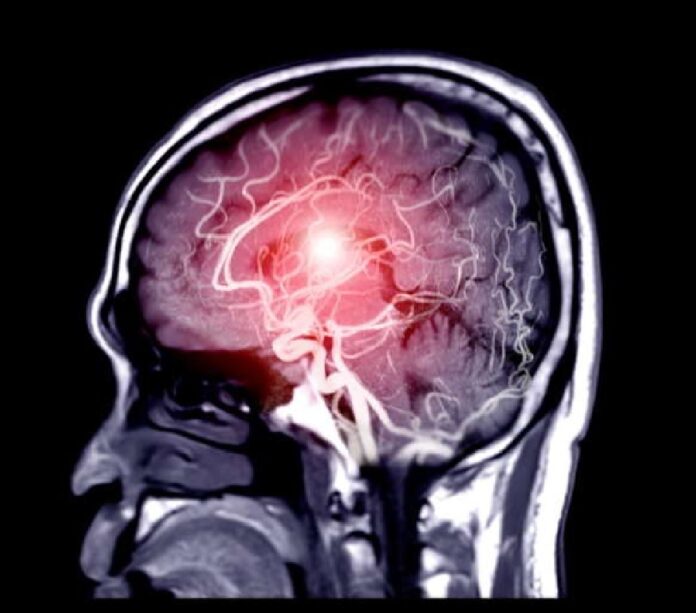

Qui è stato sottoposto a tutti gli accertamenti necessari per conoscere le origini dell’evento ischemico e dare indicazione all’intervento di trombectomia meccanica, eseguito dall’équipe della UOC di Neuroradiologia Interventistica, diretta dal prof. Sergio Vinci. Si tratta della procedura endovascolare che consente di liberare i vasi ostruiti e per la quale l’AOU è centro di riferimento nella rete provinciale dello stroke. Infatti, nelle ore successive alla trombectomia, il paziente ha recuperato perfettamente e ha ripreso a camminare regolarmente.